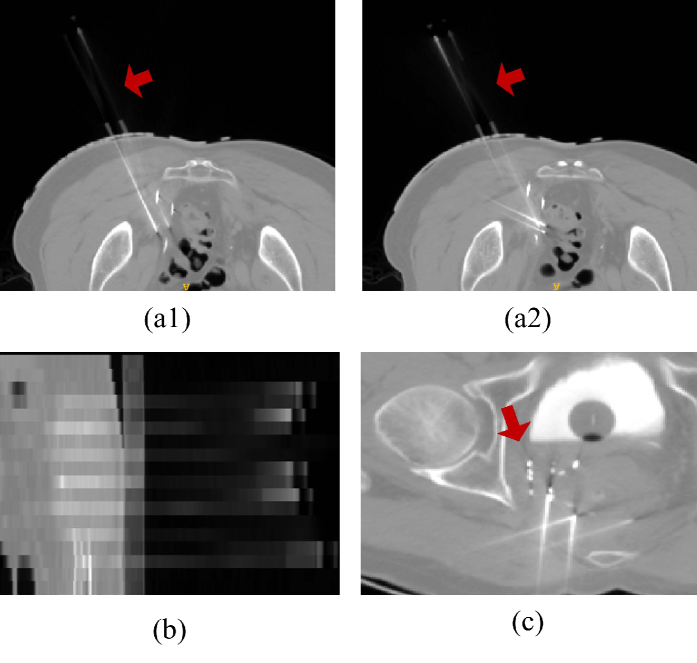

Extracting needle paths from CT images is challenging due to the partial-volume effect. This results in uneven and obscure grayscale distribution along the needle path, complicating both manual annotation and automatic segmentation, as shown in Fig.1(a1) and (a2). Additionally, needle adhesion makes it difficult to separate individual needle (Fig.1(b)). Furthermore, surrounding bone structures and previously-implanted seeds in cases of recurrent rectal cancer can have a significant impact on needle path localization (Fig.1(c)).